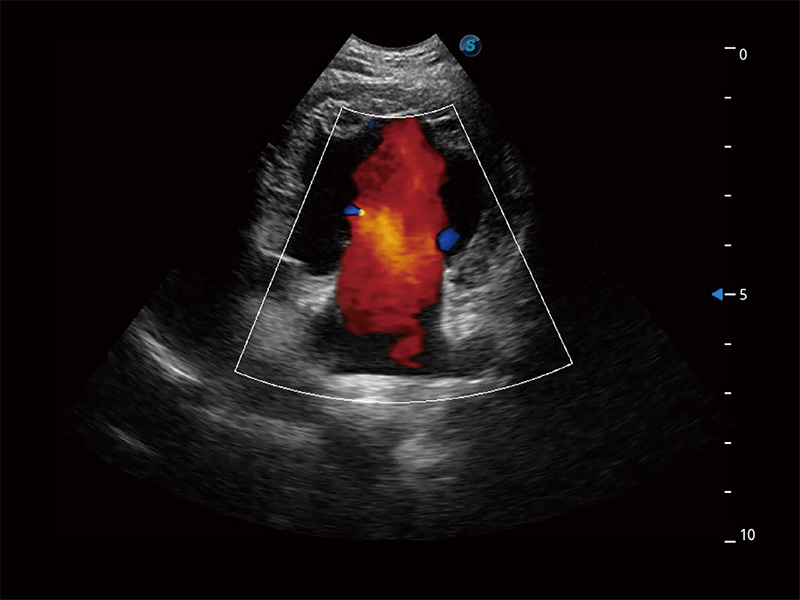

• Bright Flow 立体血流成像

在传统二维血流成像的基础上,呈现血流的立体感,具有动感的生命力之美。即便是微小的血管也能轻松应对,提高了血流的视觉敏感性。

(犬)胎儿主动脉弓立体血流